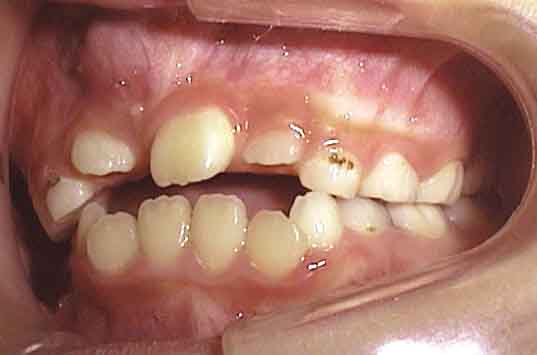

治療開始4ヶ月後